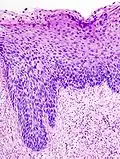

Histología

Los cambios microscópicos iniciales que corresponden al desarrollo de una neoplasia cervical intraepitelial son las displasias del epitelio, es decir, la superficie que recubre el cuello uterino, lo cual es indetectable y asintomático en la mujer.[2]

Los NIC tienen tres grados distintivos, basados en el espesor de la invasión por parte de las células escamosas:

- NIC1 (Grado I), es el tipo de menor riesgo, representa sólo una displasia leve o crecimiento celular anormal[1] y es considerado una lesión escamosa intraepitelial de bajo grado.[3] Se caracteriza por estar confinado al 1/3 basal del epitelio cervical.

- NIC2 (Grado II), es considerado una lesión escamosa intraepitelial de alto grado[3] y representan una displasia moderada, confinada a los 2/3 basales del epitelio cervical.

- NIC3 (Grado III): en este tipo de lesión, considerada también de alto grado, la displasia es severa y cubre más de los 2/3 de todo el epitelio cervical, en algunos casos incluyendo todo el grosor del revestimiento cervical. Esta lesión es considerada como un carcinoma in situ.